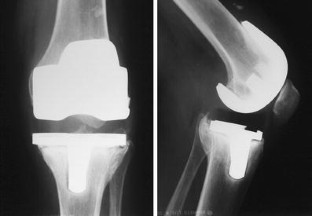

The diagnosis of Charcot arthropathy in the knee is rare. However, there is an increasing number of diabetic patients, and they are living longer due to improvements in treatment. Because neuropathic arthropathy is a late effect of peripheral neuropathy, we can expect an increasing incidence of neuropathic arthropathy. Total knee arthroplasty is the preferred choice of treatment by patients, although it may also be associated with a high incidence of serious complications. This case report presents a young female with diabetes mellitus and Charcot arthropathy of the knee managed by total knee arthroplasty and a literature review. The report encompasses a 5-year follow-up of the patient, from the first contact after knee distortion through diagnosis of Charcot arthropathy and the performance of total knee arthroplasty with outpatient controls. The diagnosis was established on the basis of the rapid destruction of the medial tibial condyle after knee distortion in a patient with neuropathy. Neuropathic arthropathy was confirmed by histology. The patient refused knee fusion and total knee arthroplasty was performed. The patient quickly achieved a painless, stable knee with a 130-degree range of motion. However, a radiolucent line appeared under the tibial component due to premature weight-bearing. The patient was ordered to refrain from weight-bearing for the next 3 months, and the knee was healed. While the management of Charcot arthropathy in the knee remains controversial, total knee arthroplasty is not a contraindication. Early diagnosis, appropriate choice of implant and operative technique, and long-term weight protection are essential.

Fig. 2